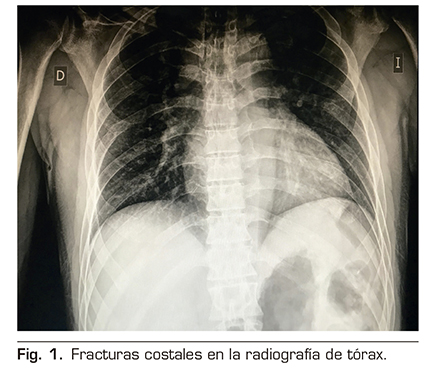

Figura 2